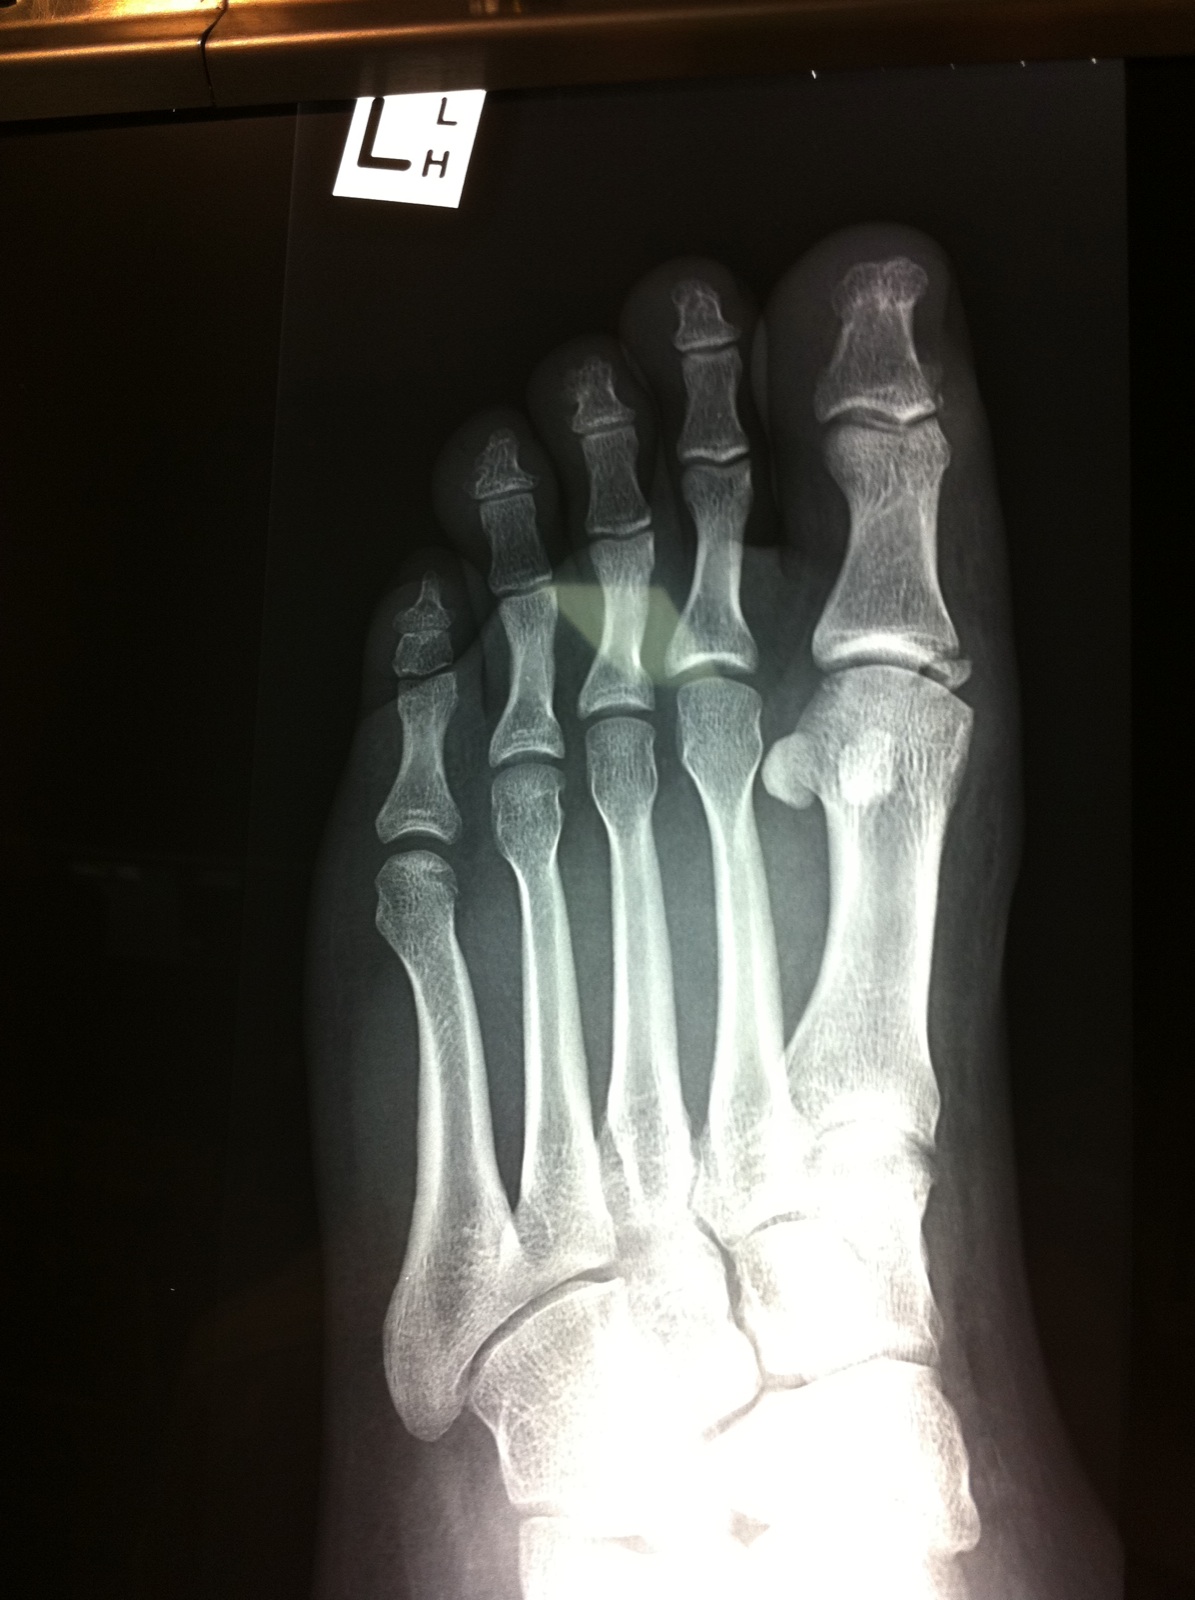

Just been to docs, and i have a brken big toe. with a chunk of bone floating. Pin/screw or Not will be 4-6 weeks in cast :x

Post by Wattie »

....

Attachments

IMG_1098.jpeg

IMG_6804.jpeg

IMG_7140.jpeg